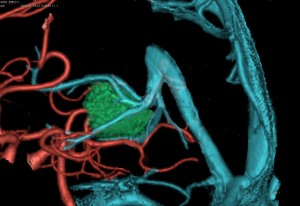

腫瘍からの導出静脈のイメージ図です。松果体腫瘍なので,松果体静脈 pieal veins(赤くぬった静脈) から導出されます,ガレン大静脈の腹側,ICVの腹側に還流します。松果体静脈の他にも第3脳室上部の静脈がICVに腫瘍静脈となって複数還流しています。

問題は,これらの静脈が腫瘍表面からいきなりガレンやICVに入ることです。

全ての手術操作を通してもっとも困難な部位であり,この部分が上手に剥離できないと,「腫瘍部分摘出」という結果になります。一方,この静脈を切断し損なったりちぎってしまうと,ICVからの大量の出血を招き,手術死亡や視床の大きな梗塞などの重篤な合併症を生じます。